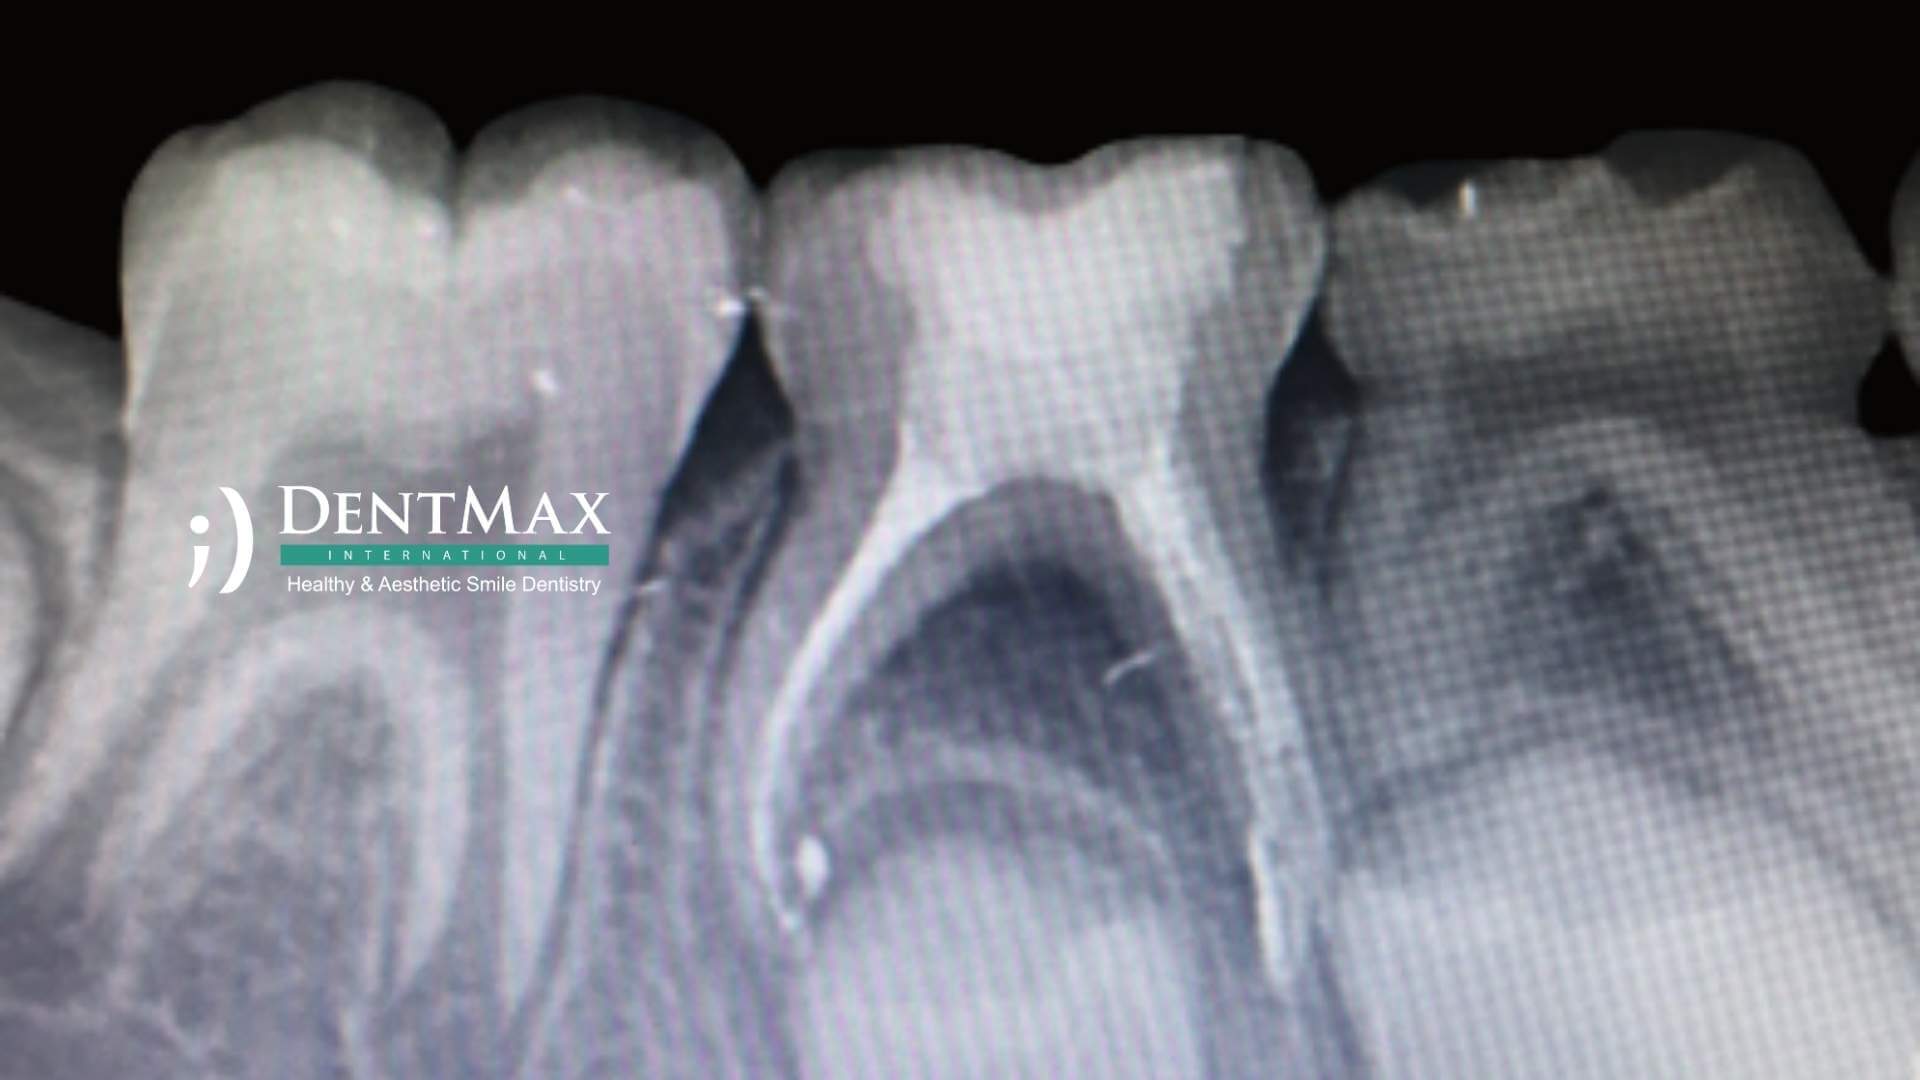

Le traitement des canaux sur les dents de lait permet de conserver les dents temporaires infectées ou traumatisées jusqu’à leur chute naturelle. Il évite les pertes précoces et favorise l’alignement des dents définitives. À la Clinique DentMax Istanbul, nos pédodontistes assurent ce soin de manière douce et adaptée aux enfants.

C’est une procédure visant à retirer la pulpe infectée ou endommagée d’une dent temporaire (dent de lait) et à la remplacer par un matériau biocompatible, afin de conserver la dent jusqu’à son remplacement naturel.

Comment se déroule la procédure ?

1. Anesthésie locale

2. Retrait de la pulpe infectée

3. Nettoyage et obturation du canal avec un matériau adapté

4. Reconstruction avec une obturation ou une couronne pédiatrique

Souvent réalisée en une seule séance